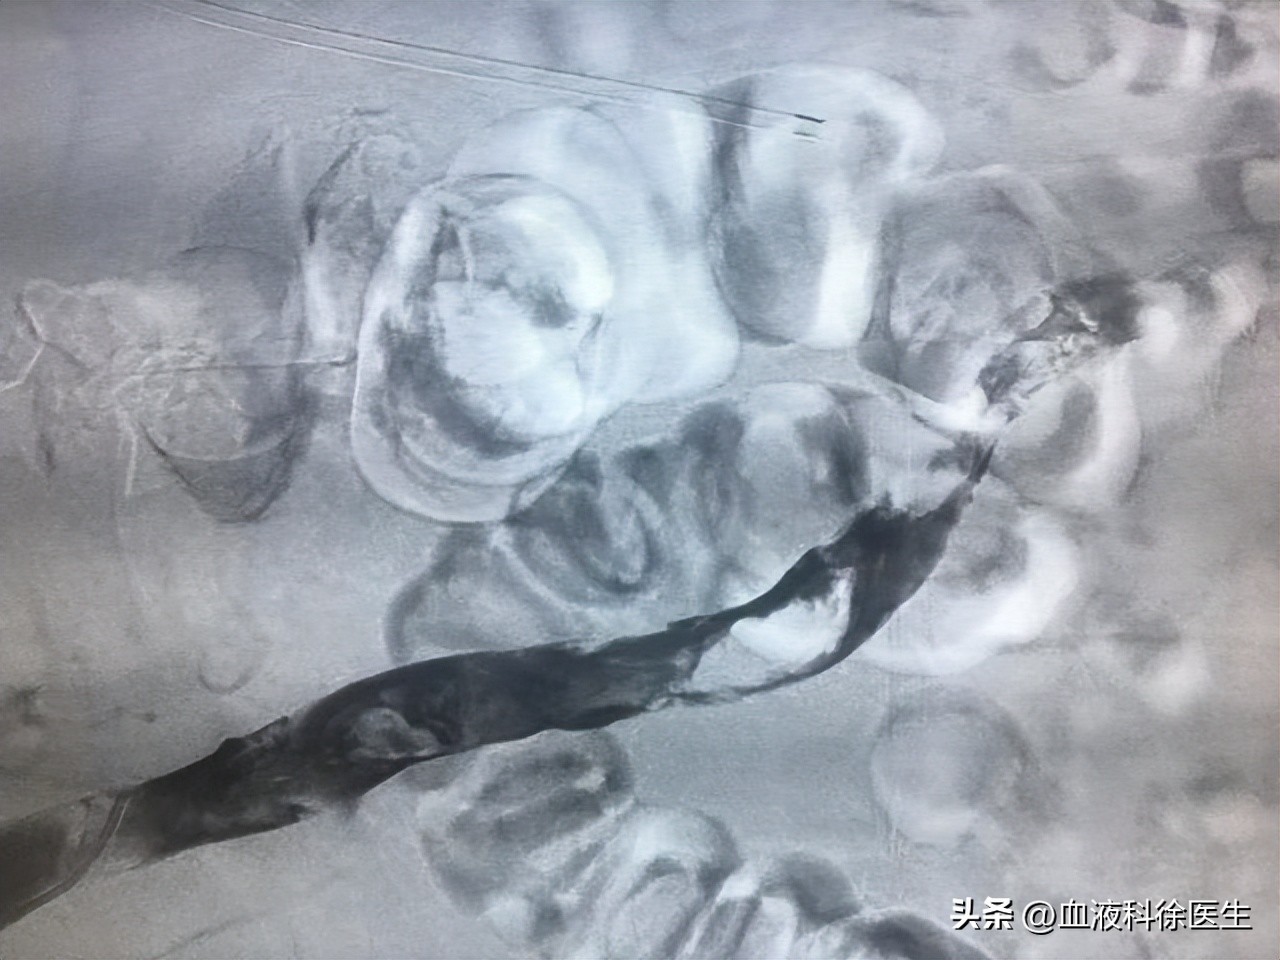

童女士在送到医院后,医院医生为童女士进行了体查,发现童女士皮肤颜色发热,脚踝处呈青紫色,下肢用手指按压时疼痛更加明显,之后医生又为童女士进行了二维灰阶超声和CT检查。

二维灰阶超声检查显示童女士的 静脉管径明显增宽,血栓呈现低-极低回声 ,而且血栓边缘处呈现漂浮状。另外,CT结果显示管腔中心性不规则形充盈缺损,管腔闭塞。医生根据检查结果判断童女士为急性下肢深静脉血栓,需要进行溶栓治疗。